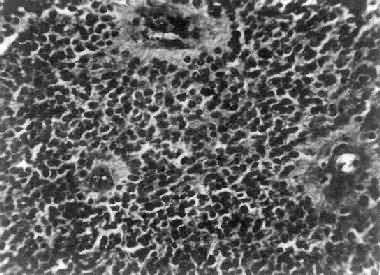

镜下,肿细胞形态多样,可相似于纤维型星形胶质细胞、原浆型星形胶质细胞和肥胖星形胶质细胞,故分别称为纤维型、原浆型和肥胖型星形胶质细胞。前二者为良性肿,后者性质介于良恶性之间。如肿细胞出现间变,细胞密度增大,异型性明显,核深染,出现核分裂像,毛细血管内皮细胞增生,则为间变性星形胶质细胞,为恶性肿

高度恶性的星形胶质细胞称为多形性胶质母细胞(glioblastoma multiforme),多见于成人。肿好发于额叶、颞叶白质,浸润范围广,常可穿过胼胝体到对侧,呈蝴蝶状生长(图16-24)。体因常有出血坏死而呈红褐色。镜下,细胞密集,异型性明显,可见怪异的单核或多核巨细胞。出血坏死明显,是其区别于间变性星形胶质细胞的特征。毛细血管明显增生,内皮细胞增生、肿大,可导致管腔闭塞和血栓形成。肿发展迅速,预后极差,患者多在2年内死亡。